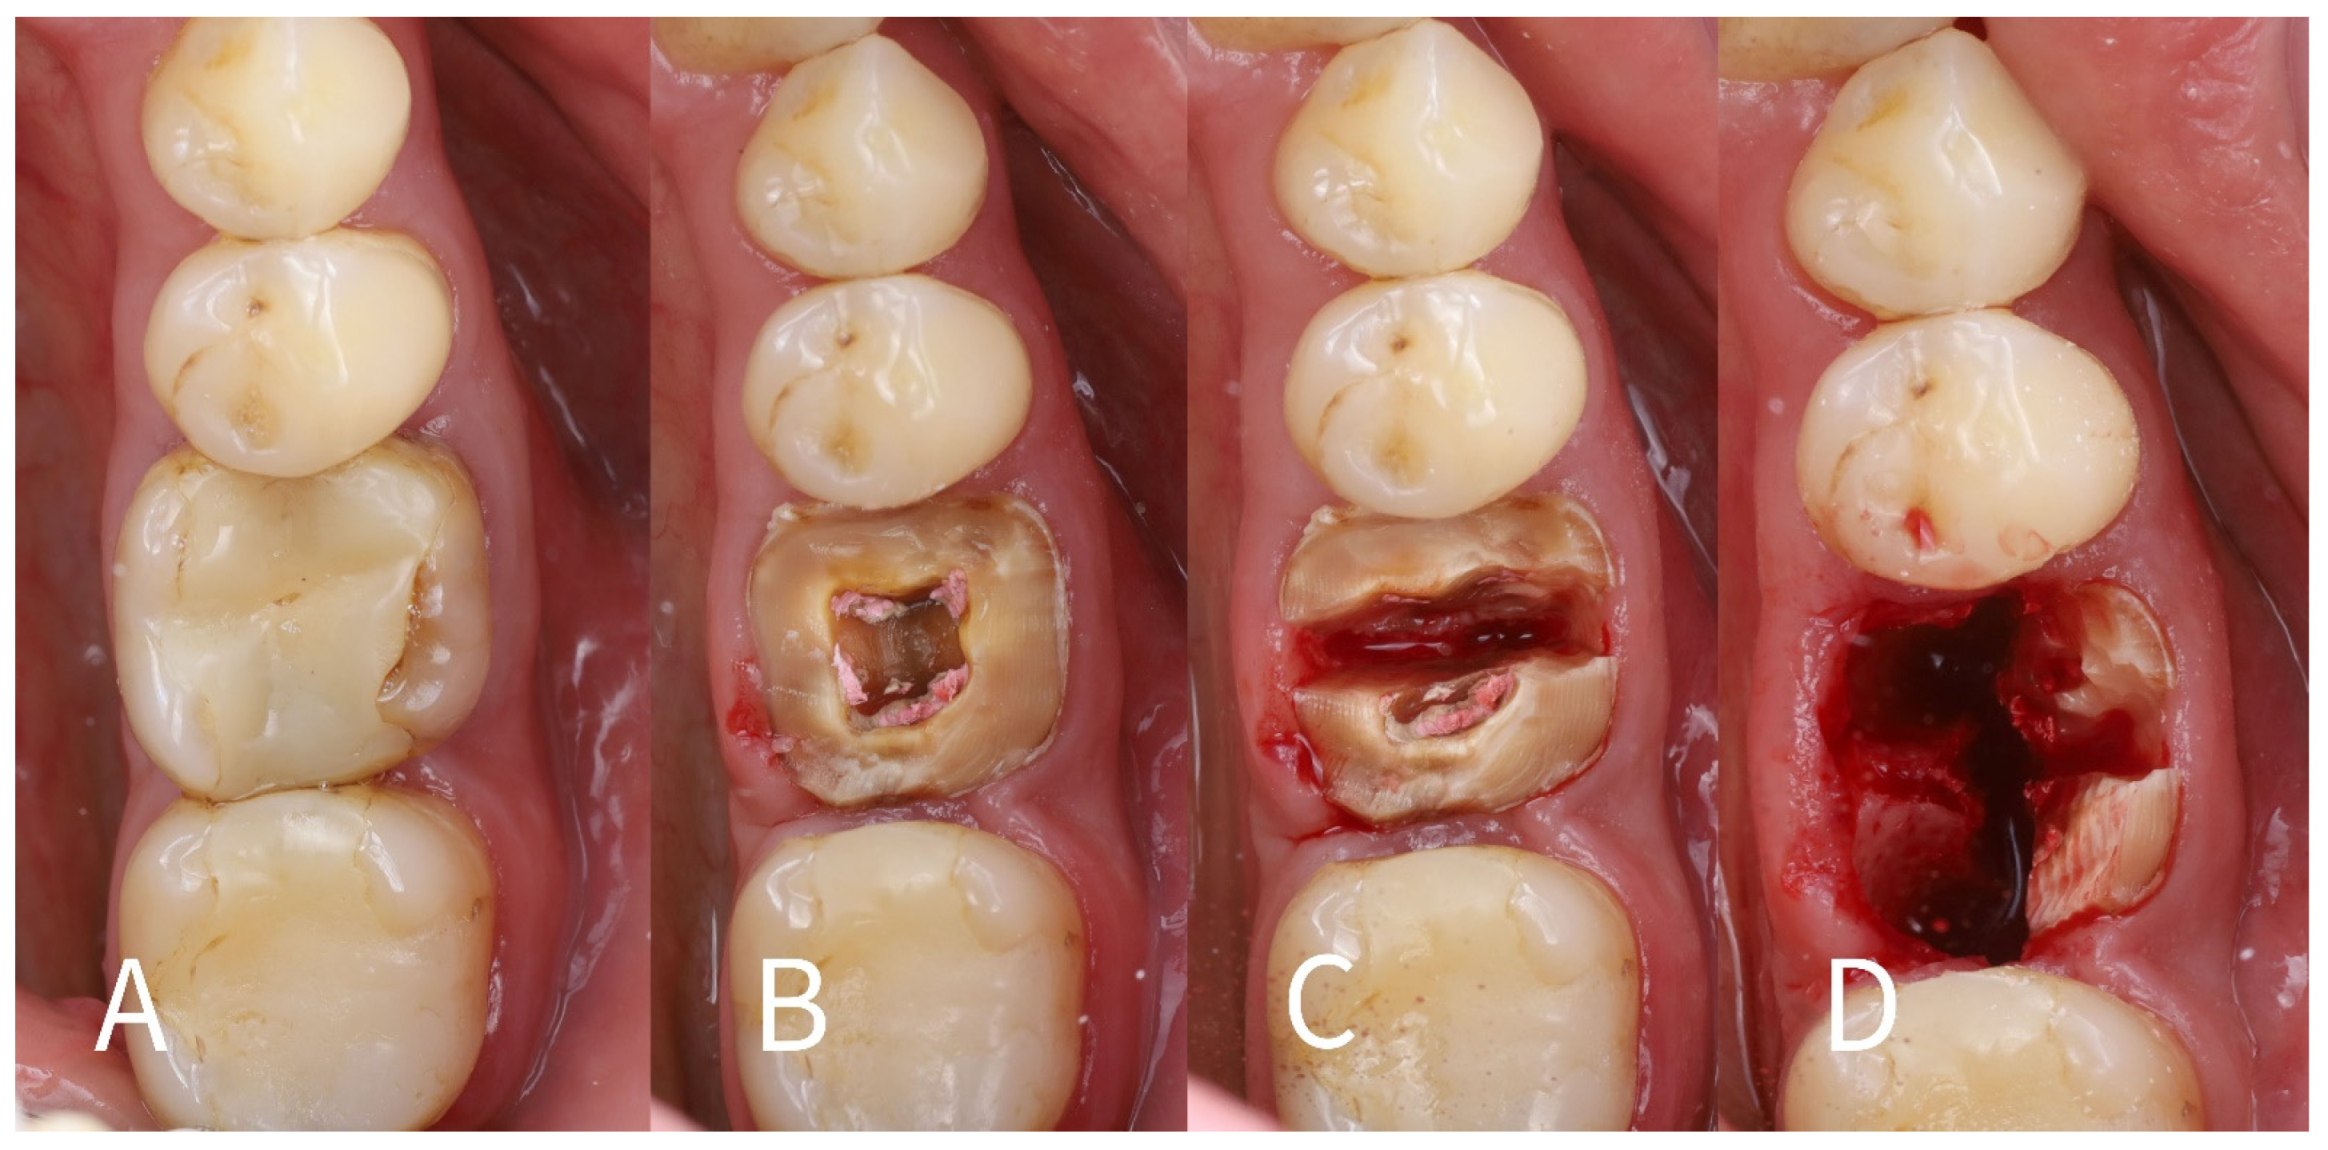

- 1.

- Root sectioning: After performing mandibular nerve block anesthesia, the crown of tooth #36 (Figure 2A) was removed (decoronation was performed) (Figure 2B). The mesial and distal roots were then separated buccolingually using a long-shanked, straight diamond bur in a high-speed handpiece with copious irrigation (Figure 2C). The preoperative CBCT was consulted to guide the depth and orientation of the cuts, accounting for the roots’ length, curvature, and angulation.

- 2.

- Partial root extraction: Each root was sectioned in a mesiodistal direction approximately 1–1.5 mm buccally from the center of each root surface to a depth of about two-thirds of the root length, using a #2 long cylinder bur from Gluckman’s partial extraction therapy (PET) surgical kit (Megagen, Seoul, South Korea). This created buccal and lingual segments for each root. The lingual root segments (along with their apices) were carefully extracted, leaving only the buccal portions of the roots in place as the “socket shields” (Figure 2D). If the lingual part fails to extract and remains in the socket still attached to the shield, it should be detached from the shield with bur #3 and extracted in the conventional way. In such cases, the bony septum can be drilled in the center to facilitate extraction.